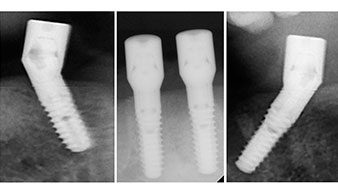

A three-dimensional cone beam computed tomography scan (CBCT, Planmeca) was performed to aid planning and minimize risks. This revealed that the quality and quantity of the available bone were sufficient for the surgery and immediate restoration using the Fast & Fixed method. Following the protocol for this concept, the implants are inserted at 35, 32, 42 and 45. Angling the distal implants by up to 45° shifts the emergence profile to posterior and generates a larger support polygon (Fig. 3).

Fast & Fixed method

Fig. 3

Following the time required for the osseointegration, the final impression of the implants could be performed and the final denture produced accordingly (Fig. 19 and 20). At this point, the dentist and patient were able to decide together whether to use a ceramic or acrylic veneer and a zirconium or metal framework. In this case, Dr. Pascu’s team decided on an acrylic veneer based on the unclear prognosis for the maxillary dentition and the fact that tooth 24 is elongated. This type of veneer is generally considerably easier to adapt and can thus be subsequently altered to reflect the new situation in the maxilla.

Osseointegration

Fig. 19

Implants

Fig. 20